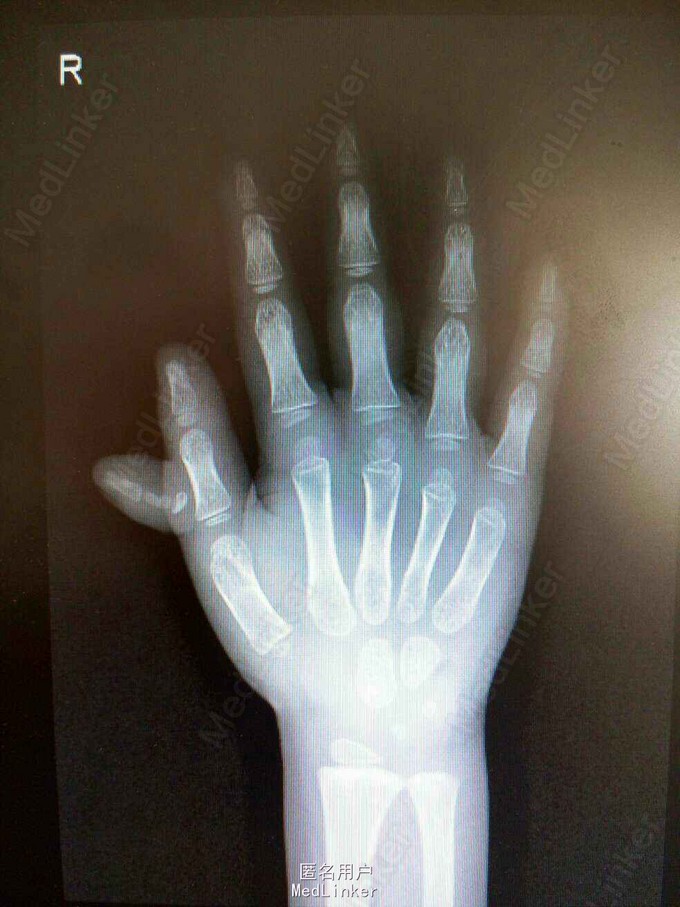

查体:右手拇指多指畸形,自右手拇指近节中部,向外侧生发出一拇指节,活动可,未触及粘连,触之无压痛,表面皮肤未见明显红肿。辅助检查:右手正斜位X光检查提示:右侧拇指多指畸形,与正常拇指无骨性连接,余右手各掌骨、指骨、腕骨形态以及骨质未见异常。各指间关节、掌指关节以及腕关节结构关系正常,关节面光滑,关节间隙无变窄。

诊断:右手拇指多指畸形 处理:全麻下行多指切除术